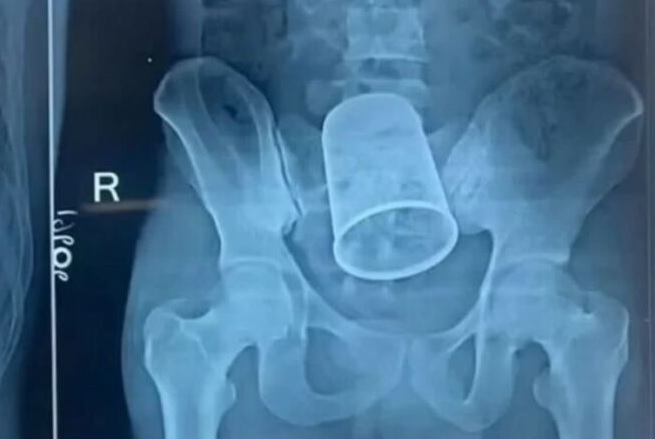

Homem introduz copo de 14 centímetros no ânus durante noitada de cachaça

Um homem de 22 anos passou por uma cirurgia de emergência após enfiar um copo de 14 centímetros de comprimento e 7 de diâmetro no ânus durante uma noitada de cachaça~.

De acordo com os médicos do Patna Medical College Hospital, da cidade de Bettiah, na Índia, o caso deixou todos sem acreditar, até que o exame mostrou o copo.

Ele chegou ao pronto-socorro às 4 horas da madrugada com dores e sangramento no reto. Foram necessários 11 médicos para retirar o copo.

O paciente agora vai usar uma bolsa de colostomia por  3 meses.